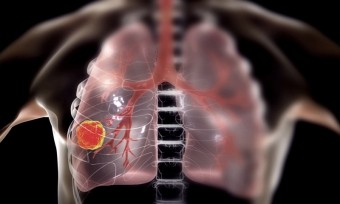

오늘은 많은 분들이 궁금해하는 폐암 초기 증상에 대해 이야기하려 합니다. 폐암은 한국인의 사망 원인 1위인 암으로, 초기에는 뚜렷한 증상이 없거나 감기와 비슷해 간과하기 쉽습니다.

폐암 초기증상 하지만 몸이 보내는 작은 신호들을 놓치지 않고 조기에 발견하여 치료를 시작하는 것이 매우 중요합니다. 지금부터 폐암의 10가지 주요 초기 증상들을 꼼꼼히 살펴보고, 건강을 위한 첫걸음을 함께 시작해 볼까요? 💨

폐암은 암세포가 커지거나 주변 기관으로 전이되면서 다양한 증상을 유발합니다. 증상이 나타났을 때는 이미 어느 정도 진행된 경우가 많으므로, 아래 증상들을 주의 깊게 살펴봐야 합니다. 다음은 폐암 환자들이 흔히 겪는 10가지 주요 초기 증상입니다.